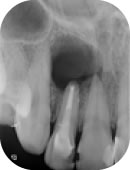

根管治療

歯の中の神経(歯髄)が壊死してしまっているなど、歯髄が残せない場合は根管治療が選択されます。

根管治療とは、歯の内部に入った細菌を除去することによって、痛みや腫れといった症状を取り除く治療のことをいいます。

根管内で増殖した菌を放置すると、歯を支えているあごの骨にまで感染が広がっていきます。さらには根尖性歯周炎という病気に発展し骨が溶けていき、最終的には抜歯するしかなくなります。

再根管治療

再根管治療は、過去に根管治療を行った歯に、再度根管治療を行うことをいいます。

過去の根管治療の際に、細菌の感染に対する処置が不十分であったり、虫歯が原因で根管が感染し根尖性歯周炎が再発した場合などに行われる治療です。

再根管治療の成功率は40%~80%といわれており、それまでの根の治療の質によって大きく左右されます。